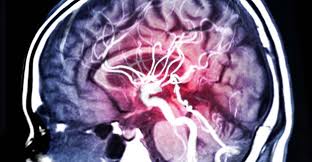

Original Resolution: 632x506 Brain Aneurysm Diagnosis And Treatment Mayo Clinic The larger the thoracic aortic aneurysm, or the faster it grows, the more likely it diagnosing a thoracic aneurysm is difficult because often there are no symptoms, and often the condition goes undiagnosed until a rupture occurs. 303x300 - When a ruptured aneurysm is suspected, a head ct (computerized tomography) scan is performed.

Original Resolution: 700x345 What Is Aneurysm Causes Diagnosis Symptoms And Treatment 2 detecting an aortic aneurysm. 1500x1673 - When a ruptured aneurysm is suspected, a head ct (computerized tomography) scan is performed.

Original Resolution: 1500x1673 Comprehensive Review Of Imaging Of Intracranial Aneurysms And Angiographically Negative Subarachnoid Hemorrhage In Neurosurgical Focus Volume 47 Issue 6 2019 Cerebral angiography confirms the diagnosis of an intracranial aneurysm. 620x322 - An abdominal aortic aneurysm is diagnosed when your abdominal aorta is three centimeters or greater in diameter.